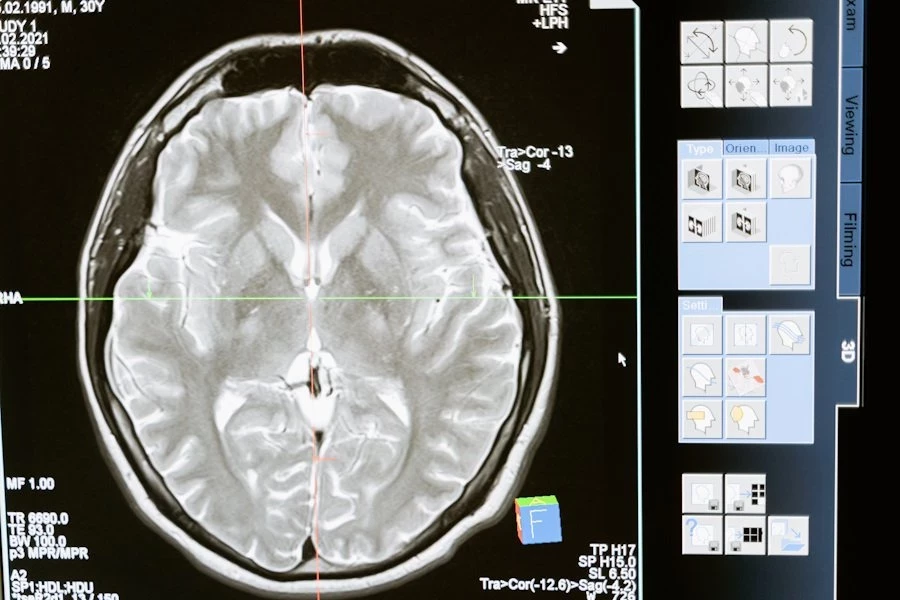

Согласно изданию NYULangone, в рамках исследования AWARE-II, проведённого с 2017 по 2020 год в США и Великобритании, изучались 567 пациентов, переживших остановку сердца. Менее 10% из них удалось стабилизировать настолько, чтобы выписать из больницы, однако 40% выживших вспомнили состояние сознания, возникшее во время СЛР. У 85 из этих пациентов была зафиксирована мозговая активность с использованием электроэнцефалограммы (ЭЭГ), которая продемонстрировала пики в гамма-, дельта-, тета-, альфа- и бета-волнах — все они связаны с когнитивными функциями.